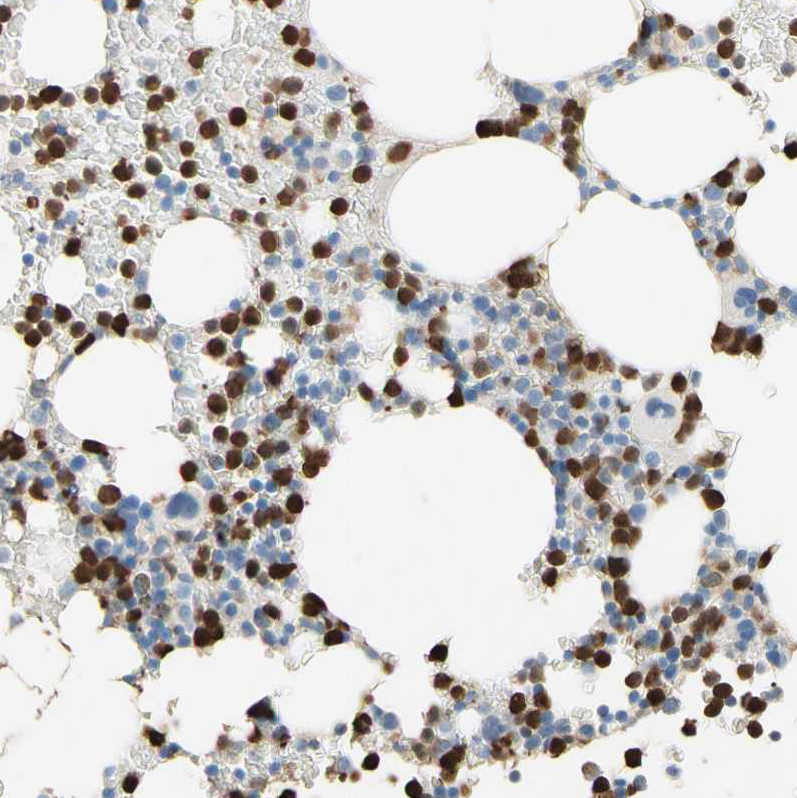

Immunohistochemistry analysis in human bone marrow and cerebral cortex tissues using HPA010547 antibody. Corresponding NFKBIZ RNA-seq data are presented for the same tissues.